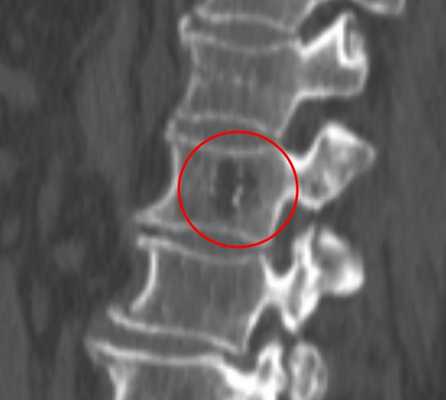

Небольшая сосудистая опухоль в боковых отделах тела первого поясничного позвонка. При компьютерной томографии выявлен гиподенсный участок плотностью -25…-30 единиц Хаунсфилда, с типичными утолщенными и «разреженными» трабекулами губчатого вещества.

В зависимости от количества периваскулярного жира плотность гемангиомы может колебаться от +200 единиц Хаунсфилда до -40 и меньше, но практически никогда не достигает плотности жировой ткани (-100 единиц Хаунсфилда). В структуре опухоли видны множественные разреженные и утолщенные до 1-3 мм трабекулы, дающие характерный «мелкоточечный» рисунок на аксиальных срезах и «полосатый» рисунок на аксиальных и корональных изображениях. После введения контрастного вещества строма опухоли может усиливаться, зачастую весьма значительно. Наибольшую плотность сосудистые опухоли имеют в артериальную фазу контрастирования. Контраст из сосудистых лакун вымывается быстро, поэтому уже в венозную фазу плотность образования существенно снижается.

Рентгенологическое описание гемангиомы позвоночника может быть следующим: «в позвонке выявляется участок низкой интенсивности, с ровными краями, четкими контурами, неоднородной структуры за счет наличия утолщенных трабекул губчатого вещества». Здесь также прослеживается зависимость между количеством жира и рентгеновской плотностью - чем больше жира, тем выше контраст с окружающим губчатым веществом.